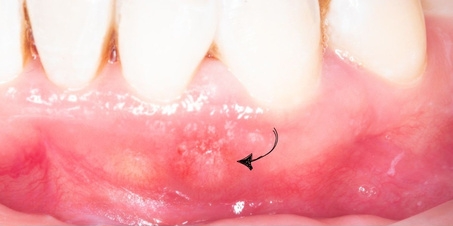

Persistent Infection from root treated 31

CBCT summary of tooth 31:

- Large periapical radiolucency measuring 12.4mm at the widest width.

- Perforation of buccal bone

- Lesion involving apex of 32 and 41 (adjacent teeth)

- Flap design (Papilla-based incision flap) to reduce post-operative gingival recession.